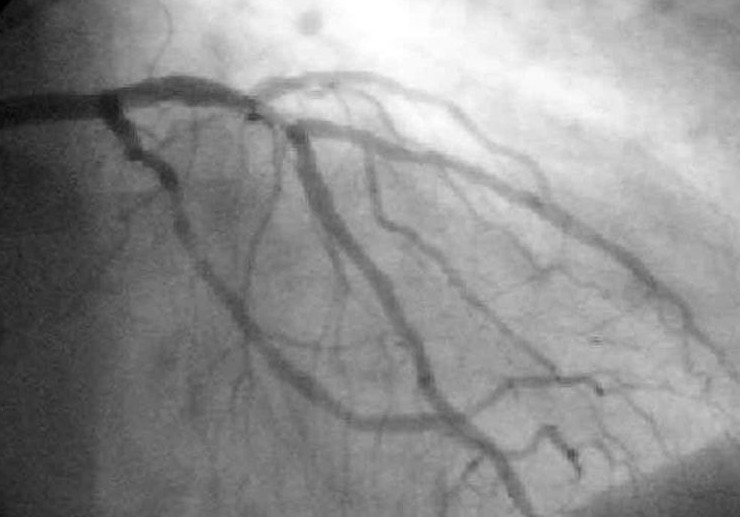

9. Коронарная ангиография: ошибка, спасшая сердца

Кардиолог Ф. Мейсон Сонс в 1958 году случайно ввёл контрастное вещество прямо в коронарную артерию пациента. Он испугался, что убил больного, но тот… остался жив.

Так врачи поняли, что можно безопасно исследовать сосуды сердца и появился метод коронарной ангиографии.